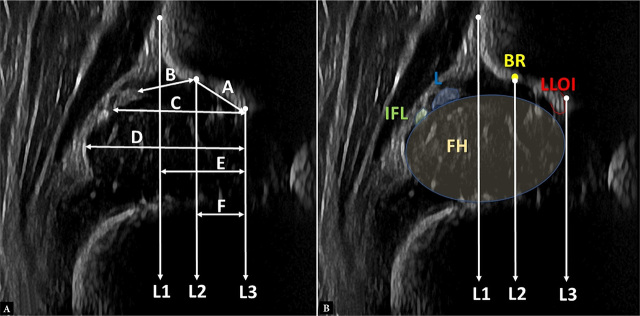

Material and methods: A total of 60 Graf type II hips and 124 randomly selected Graf type I hips, matched to the gestational age at delivery, birth weight, delivery mode, and age at the time of the examination, were identified through our hip screening service, during a period of two years. The images were diagnostically suitable, following anatomical identification and usability check, according to Graf. Anatomical landmarks including the lower limb of the os ilium, the bony rim, the silhouette of the os ilium, the labrum and the femoral head's borders, were used to determine the measurements and ratios which quantified their inter-relationships.

Results: The indices which differed significantly between type I and type II hips included: (a) the width of the "bony roof" (cut-off value 5.91 mm, sensitivity: 75%, specificity: 70%), (b) the ratio of the width of the "bony roof" to the femoral head's width (cut-off value 0.40, sensitivity 83%, specificity 71%), and (c) the ratio of the cartilaginous acetabular roof's width (including the labrum), to the width of the femoral head (cut-off value 0.450, sensitivity 82%, specificity 67%).